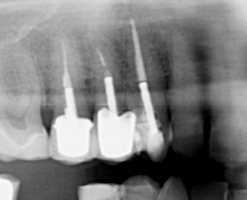

On your initial appointment the dentist will locate the offending tooth and take an x-ray in order to show the roots of the tooth, to see how far the decay has travelled and if there is an abscess present. A course of antibiotics may be given to clear the abscess before the treatment is started as the abscess will reoccur if the treatment is NOT carried out.